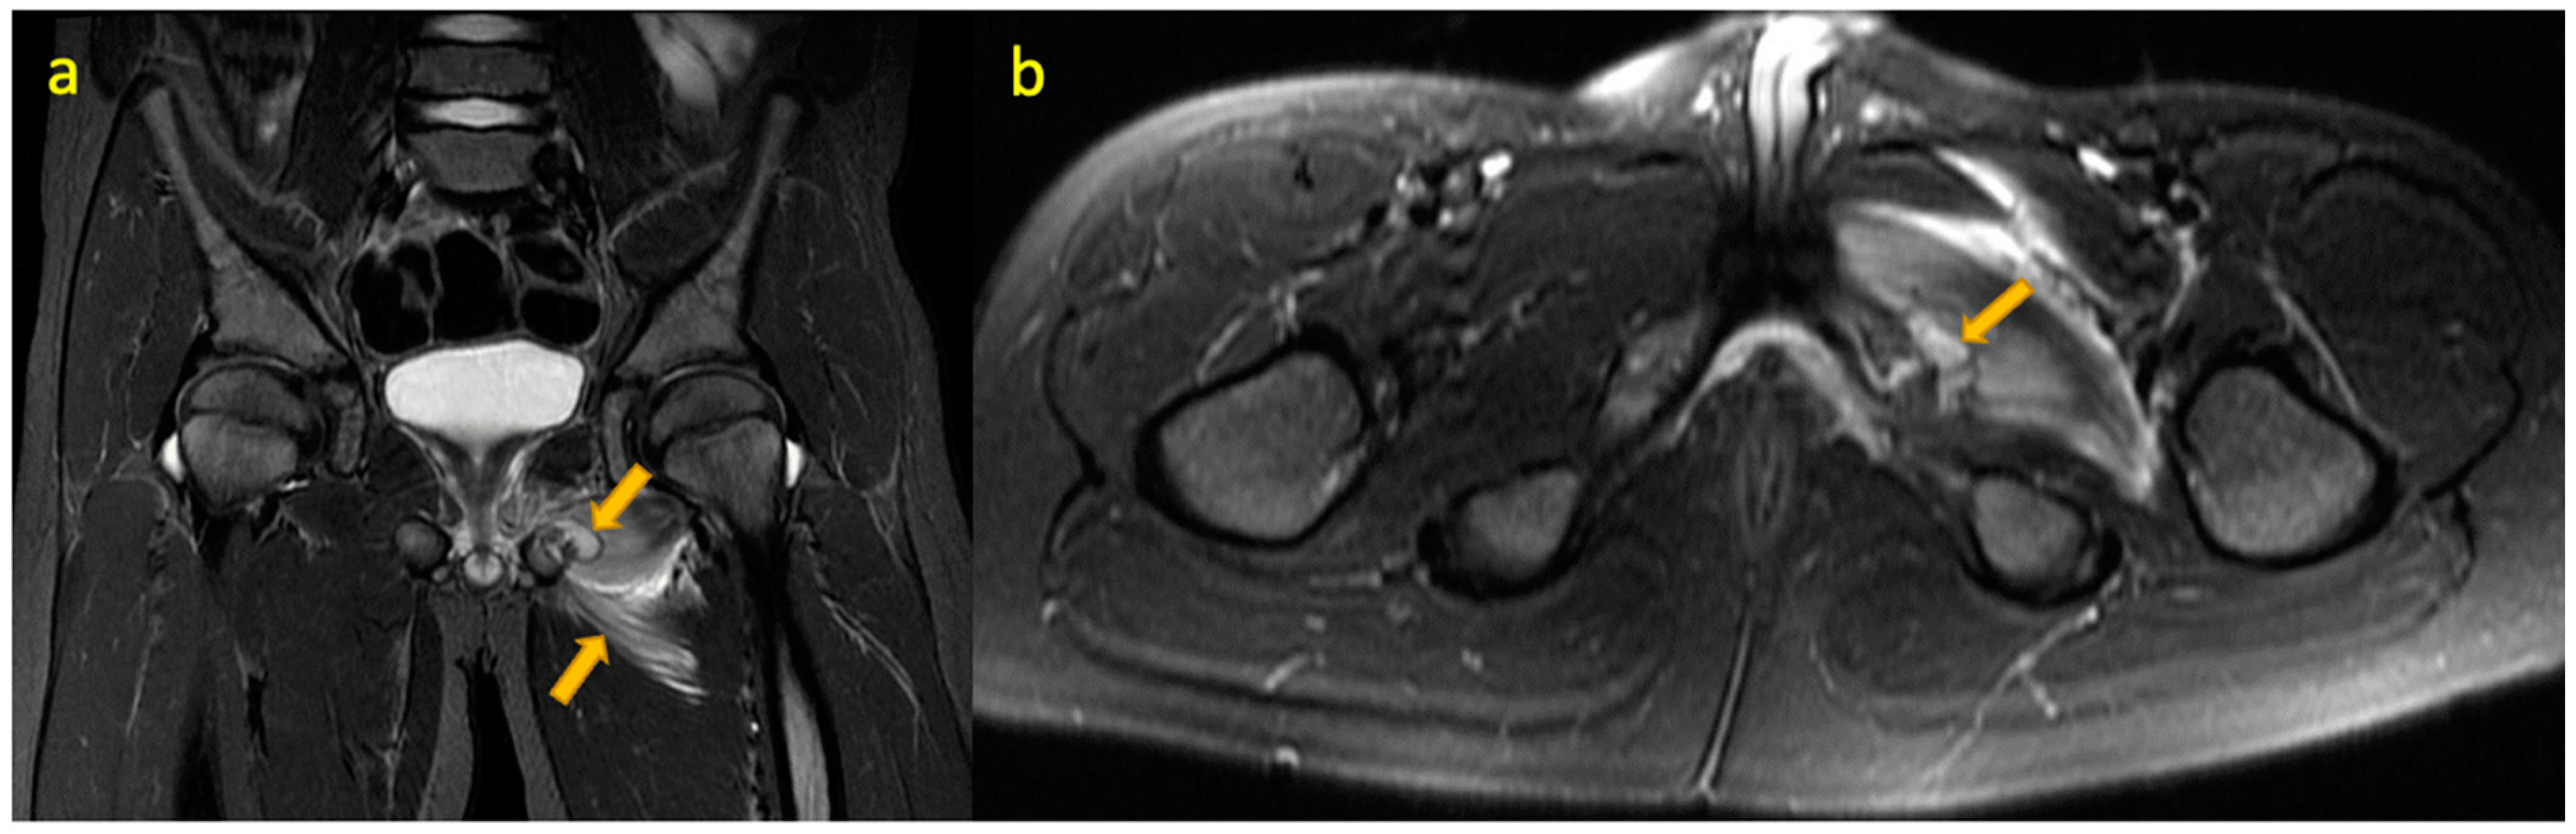

6. Rectus Femoris Avulsion Fracture